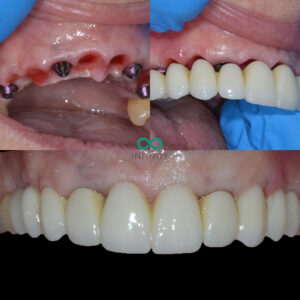

During the treatment we provided our patient with fixed teeth from the very beginning of her treatment plan. She never spent any time without teeth. In fact, on the very same day that she had her teeth removed, we provided her with fixed dental implant supported teeth.

Dental implants, gums and bone grafts all take on average 3-6 months to fully stabilise after healing. This means it can take upto 6 months to provide a perfectly fitting set of teeth to the dental implants. During this time however, our patient continued to wear her initial implant supported teeth meaning she still had a lovely smile and could chew properly during this treatment time.

After the 6 months had passed, we carefully sculpted her gum line with all the volumous gum graft that had now worked and fully healed. The contours we had created were carefully designed to mimic her natural smile design that we planned using our digital smile desgin programmes. Following this careful gum sculpting process, we made a truly bespoke implant bridge that looked and felt as natural as is possible. The patient was delighted and we were especially proud of the fit between the gums and the implant teeth. That new gum line was healthy, natural and therefore very easy for the patient to clean and maintain daily with a normal electric toothbrush.

That is the thing with gum contouring – it enables us to provide natural teeth. Natural is important because it often means it will last longer and be more ‘natural’ to maintain too.